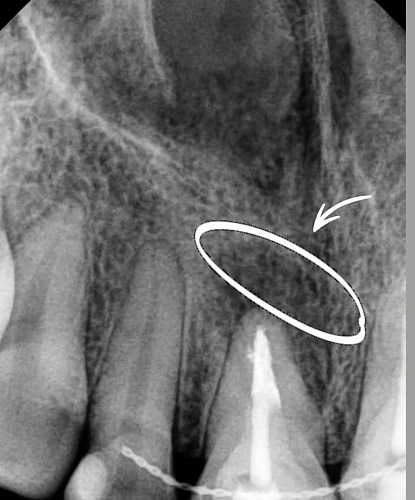

Пациент обратился с жалобами на болезненные ощущения в зубе при нажатии.

После осмотра и рентгенологической диагностики был выявлен участок разрежения костной ткани, (хронический периодонтит). В ходе микроскопической ревизии инфицированного содержимого корневого канала была проведена санация, а затем пломбирование.

Контрольный осмотр через 6 месяцев показал полное заживление костной ткани и восстановление здоровья зуба.